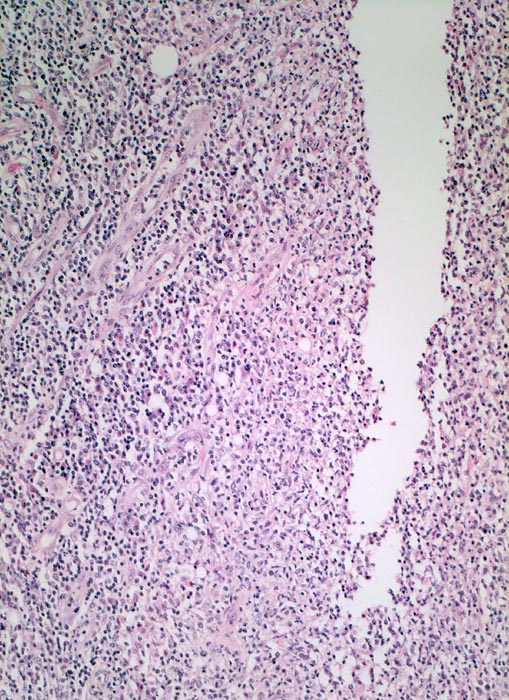

In Biopsien der Darmschleimhaut zeigen sich als Zeichen der Chronizität eine Architekturstörung, reepithelialisierte Schleimhautdefekte und metaplastische Veränderungen. Typisch für den Morbus Crohn sind entzündlich veränderte Schleimhautabschnitte neben weitgehend normaler Schleimhaut. In der Lamina propria findet sich ein verdichtetes gemischtes Infiltrat bestehend aus Lymphozyten, Plasmazellen, Makrophagen, neutrophilen und eosinophilen Granulozyten. Typisch für chronisch entzündliche Darmerkrankungen ist eine basal betonte Lymphoplasmozytose der Lamina propria. Die neutrophilen Granulozyten finden sich herdförmig in der Lamina propria, im Kryptenepithel (Kryptitis) und als Ansammlung in dilatierten Krypten (Kryptenabszess). Erhaltene Schleimhautabschnitte zwischen ulzerierten Arealen und Granulationsgewebe imponieren als entzündliche Pseudopolypen.

Befunde in der Mukosa wie epitheloidzellige Granulome, aphthöse Ulzera und Erosionen und fokal aktive Entzündung sind nicht spezifisch für den Morbus Crohn. Jene histologischen Aspekte, welche die Erkrankung am besten charakterisieren, sind in der Darmwand gelegen und lassen sich an einer endoskopisch gewonnenen Biopsie nicht nachweisen (fissurale, spaltförmige Ulzera, submukosales Ödem mit Lymphangiektasien, submukosale Fibrose, transmurale Entzündung mit lymphoidzelligen Aggregaten, neuromuskuläre Hypertrophie mit Wandverdickung (> 364), subseröse und submuköse Granulome (> 1133)).

• Transmurale Entzündungsinfiltrate mit Lymphfollikelbildung.

• Zahlreiche epitheloid-riesenzellige Granulome in allen Wandschichten.

• Verdichtetes lymphoplasmazelluläres Entzündungsinfiltrat in der Lamina proria.

Neutrophile Granulozyten in der Lamina propria (aktive Entzündung) und Gewebseosinophilie (vermehrte eosinophile Granulozyten in der Lamina propria).